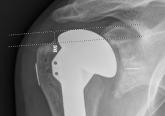

Radiographic Study of Humeral Stem in Shoulder Arthroplasty After Lesser Tuberosity Osteotomy or Subscapularis Tenotomy